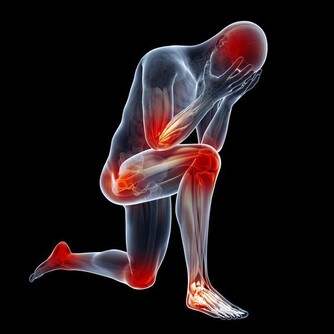

據臨床觀察,白血病患者的常見症狀包括體重異常減輕、疲倦乏力、呼吸急促、淋巴結腫大、胃部腫脹、發熱盜汗、骨痛或關節痛、頻繁反复地感染等。而患者也會感到皮膚組織瘙癢難忍,或是非常容易造成淤青或出血。如果發現自己的皮膚有類似的情況出現,一定要立即檢查,因為許多人都會忽視自己皮膚上的小問題。

多發性骨髓瘤是一類會抑制人體生產出健康血細胞的癌症。臨床研究表明,多發性骨髓瘤會損傷到患者身體的多個部位,常見的是脊椎、顱骨、骨盆,以及肋骨。在發病初期,患者可能不會出現任何異常症狀。

隨著病情惡化,患者逐漸會感到自己的骨頭在隱隱作痛,骨骼似乎非常脆弱,而且會感到疲倦乏力,刷牙時也會引起牙齦出血,女性患者在經期間的排血量也會異常增多。